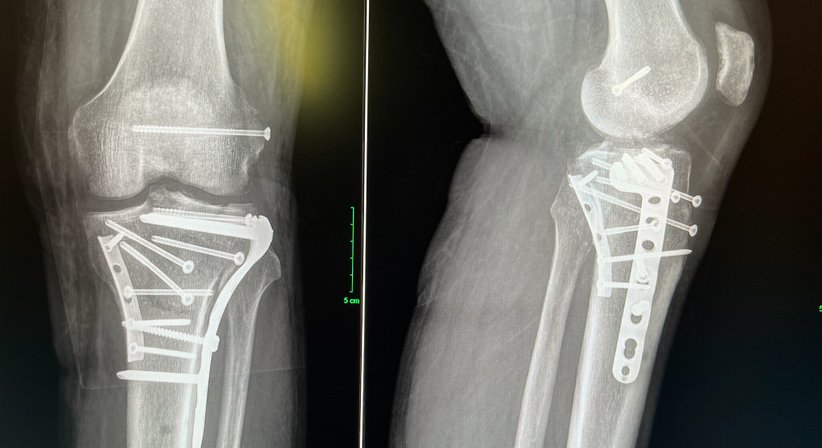

Behandlung von Frakturen des Ober- und Unterschenkels im Kniegelenksbereich